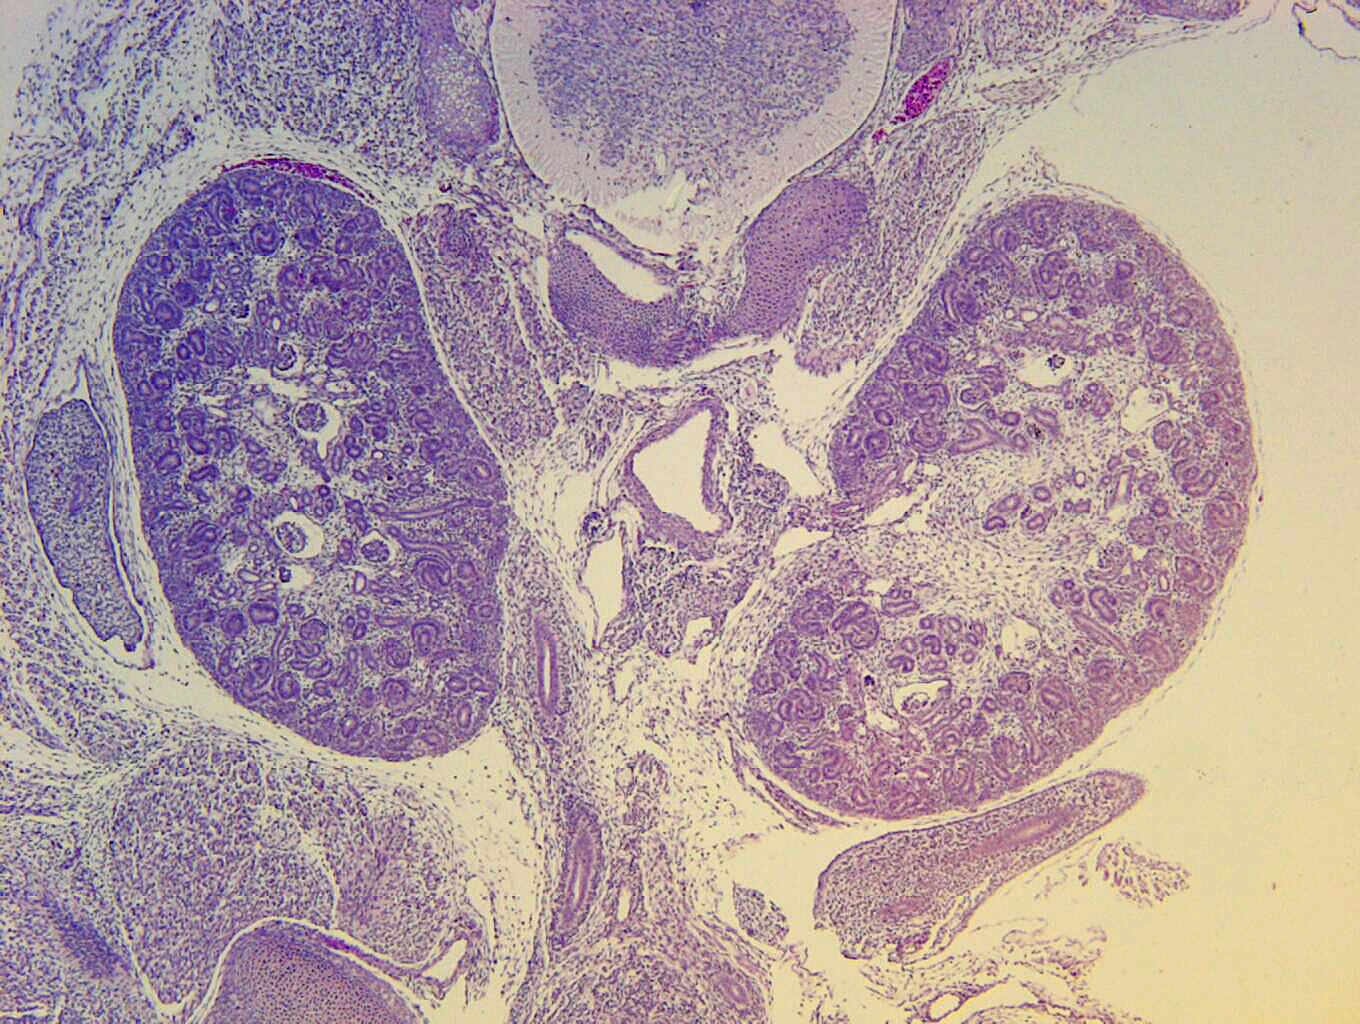

Caption EFIC Summary

Copyright This image is from the Laboratory of Dr. Cecilia Lo, a member of the Cardiovascular Development Consortium (CvDC), Bench to Bassinet (B2B) program of the National Heart Lung and Blood Institute (NHLBI), and is displayed with the permission of the authors. J:175213

Tbc1d32b2b2284Clo TBC1 domain family, member 32; Bench to Bassinet Program (B2B/CVDC), mutation 2284 Cecilia Lo

Tbc1d32b2b2284Clo/Tbc1d32b2b2284Clo C57BL/6J-Tbc1d32b2b2284Clo